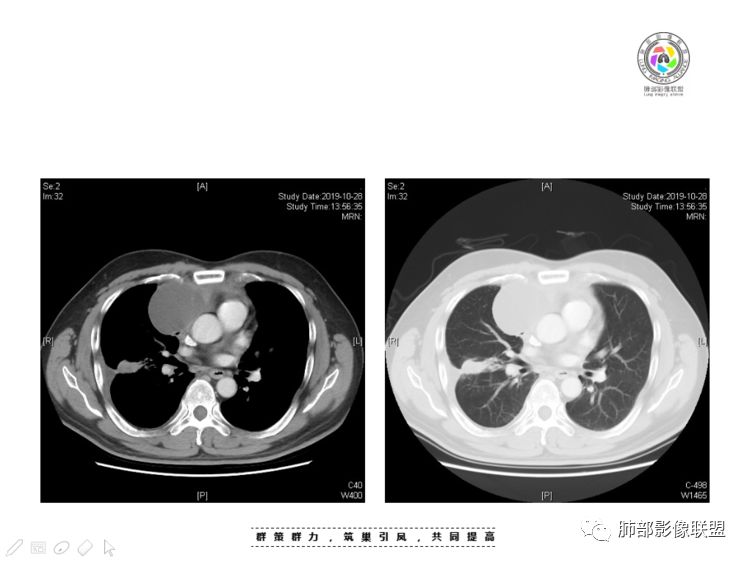

穿越七海的风:右前纵隔占位,恶性肿瘤,生殖来源?右肺实变是占位or肺不张?考虑为部分肺不张FeNo:右前纵隔占位,右肺结节,胸膜凹陷,小尾巴,右肺不张,考虑恶性杨旭华:恶性,前纵隔肿物,与血管关系密切,上腔静脉变窄,右肺野一元论考虑叶间裂增厚,恶性胸膜间皮瘤可能大小丽:到底是纵隔来源还是胸膜来源?我怎么倾向于胸膜来源,和叶间胸膜关系密切,而且纵隔内上腔静脉是向内侧推移。胸膜肿瘤(间皮瘤?SFT?)包裹性胸腔积液?马春平(张家港市一院胸外科):前纵隔占位,左无名受压,右大量胸腔积液可能是胸导管汇入处侵犯受压,考虑纵隔鳞癌孙冰伟:右上纵隔占位,也感觉和叶间胸膜关系密切,右侧胸膜局限性增厚,考虑恶性可能性大灵:前纵隔占位,血性胸水,胸膜凹凸不平,查见肿瘤细胞,结合免疫组化考虑胸腺癌。鉴别胸膜间皮瘤。采莲:右前上纵膈旁可见类圆形肿块,纵隔血管内移,感觉来源于胸膜,肿块内密度低,似水样密度,右侧胸膜广泛增厚,少量胸腔积液。心包少量积液。考虑胸膜间皮瘤,鉴别肺癌并胸膜转移?水晶石头:患者中年男性,胸闷15天。有“高血压、慢性肾小球肾炎”病史。查肿瘤标志物正常,胸水提示渗出液,胸水病理查见瘤细胞。胸部CT:右肺上叶后段结节、斑片影,见胸膜牵拉、包裹积液及部分纤维条索灶,似见卫星灶,右侧胸膜增厚。前纵隔脂肪密度增厚,右侧可见类圆形低密度(液体)肿块,边缘光滑。综合考虑右肺腺癌并胸膜转移,结核可能。周太狼:考虑纵隔胸膜来源肿瘤,恶性,胸膜间皮瘤伴转移?徐飞:中年男性,影像为右侧胸腔及叶间积液,叶间胸膜增厚轻度强化。前纵隔右侧心缘旁团块,可见坏死。胸水见癌细胞,综合考虑恶性,胸腺癌伴转移。小赵:中年男性,血性胸水,常规查见癌细胞,李凡他实验阳性。胸部CT示前纵隔见不均匀密度影,与邻近大血管分界不清,囊变坏死明显,增强扫描呈不均匀强化,心包及右侧胸膜增厚,并心包及右侧胸腔少量积液。综合考虑胸腺癌。右肺中叶病变周围见多发纤维条索,支气管部分进入病灶,考虑炎性病变。流心明智:患者,男性,50岁。胸闷15天。高血压20年,慢性肾小球肾炎15年。肿标正常,胸水提示渗出液,胸水查见癌细胞。胸部CT:右肺肿块影,斑片影,索条影,可见胸膜牵拉、多发包裹积液,纵隔上腔静脉受累,心包受累。综合考虑:ROSE似腺?考虑右肺腺癌并胸膜转移,心包受累。鉴别胸腺Ca、淋巴瘤,纵隔病变不懂,等老师们精彩分析。王秀仙:前纵膈囊实性肿块,与纵膈分界不清,心脏大血管及上腔静脉受压向内后移,右侧后胸膜、侧胸膜增厚,右侧叶间裂不规则增厚,心包积液,根据腔静脉移位情况,考虑纵膈胸膜来源恶性肿瘤,胸膜间皮瘤?鉴别胸腺癌并胸膜转移。高广飞:上纵隔占位,右侧叶间胸腔积液,需考虑恶性自信人生:多发囊实性病灶,包裹性积液,考虑胸膜来源 只是没有看到壁结节,恶性胸膜间皮瘤巴伟:前上纵隔占位,胸膜及心包结节,考虑胸腺瘤或癌,右肺病灶,先考虑陈旧炎性病变。Lenle董:前纵隔占位,部分边缘模糊,病灶内囊变?坏死?上腔静脉受侵,考虑胸腺癌;叶间片状影,强化明显,炎性考虑。常志强:前纵隔囊实混杂密度肿块,边界不清,实性部分强化明显,结合胸水内见癌细胞,考虑恶性肿瘤伴转移。飞鹰行动:前纵隔占位,软组织密度及囊性密度,实性部分密度均匀,致密,病灶与周围血管分界不清,增强后病灶强化有类似不温不火强化,部分血管受侵犯,右肺见肿块样病变及条索状病变,一元论,考虑淋巴瘤,二元论,考虑胸腺瘤B2—B3伴右肺病变。尽量一元论考虑,淋巴瘤可能。看图说话:右肺索条病灶,边缘膨隆,胸膜牵拉,考虑右肺癌伴胸膜转移。晨:前纵隔囊实性肿块,与纵隔分界不清,右侧后胸膜、侧胸膜增厚,右侧叶间裂不规则增厚,考虑纵隔胸膜来源恶性肿瘤,考虑胸腺癌并胸膜转移。丽:中年男性,前纵隔囊实性肿块,呈偏心性生长,临近大血管受压推移,增强后实性部分不均匀强化,心包可见条形积液,考虑胸膜来源恶性肿瘤,胸腺癌可能大。另右肺多发斑片状高密度影及实变密度影,实变影呈均匀强化,右侧胸膜局限性增厚,考虑炎性病变。小飞:右前纵隔囊实性占位,实性部分明显强化,右侧叶间胸膜增厚,右侧胸腔积液,心包积液,考虑恶性胸腺瘤!尘缘:支持恶性胸腺瘤(囊实性肿块,实性强化,且侵犯纵隔,脂肪间隙模糊)伴肺内及胸膜转移。浪迹天涯:考虑侵袭性胸腺瘤——胸腺前纵隔占位,周围脂肪间隙模糊不清。尘缘:不除外另一种可能:二元,肺内腺癌合并胸膜转移,纵隔的畸胎瘤可能。一米阳光:晨读中年男性,右肺结节影,叶间裂及胸膜增厚牵拉,右侧胸水。心包多发结节改变。胸水查见癌细胞。考虑,腺癌并转移。鉴别,胸膜间皮瘤并转移前纵隔囊实性占位,二元考虑。心灵鸡汤:老年男性,右肺中叶外段长条状软组织密度影,边缘膨隆,邻近胸膜牵拉,部分胸膜有栽脏,右中叶外侧段支气管堵塞,常规考虑恶性肿瘤,腺癌可能,结核、鳞癌不除外,另右肺上叶斑片影,小叶性肺不张?右前纵隔囊实性不规则形密度影,其内见部分脂肪样极低密度影,与邻近血管边界不清,心包外膜有侵犯,增强未见纵隔窗平扫,实性及分隔见增化,其内低密度影未强化,考虑低度恶性纵隔肿瘤,间皮瘤可能,畸胎瘤、淋巴瘤待排,建议支气管镜及穿刺活检。曹志勇:右前纵隔考虑来源于胸膜的恶性肿瘤,右肺内病灶考虑鳞癌,二元德芙~云味:中年男性,右肺见结节、斑片影,右侧包裹积液、胸膜牵拉,纤维条索,前纵隔囊性占位,考虑腺癌、并转移。欧阳英:右前中纵隔囊实性肿块及右肺内结节灶,支持恶性肿瘤,胸腺癌并肺内转移可能张延军:前纵隔见不规则软组织影,密度不均,右侧缘见囊变区,纵膈及侧胸壁胸膜增厚,增强呈不均匀强化,右肺中叶见结节灶,近段支气管阻塞,叶间胸膜不规则增厚,考虑1:右肺中叶腺癌伴纵膈及胸膜转移;2:前纵膈侵袭性胸腺瘤并胸膜侵犯,中叶炎性改变?彭君:老年,前纵隔占位 ,坏死边缘清, 侵犯心包 右侧胸膜及叶间胸膜结节 ,少量胸水, cea不高 ,考虑恶性, 间皮瘤可能 ,转移待除外。毛勤香:恶性没问题,胸水查见癌细胞,一元还是2元,右肺中叶肿块,边缘毛糙,局部似有毛刺,周围有粘连,右侧胸膜腔少量积液,胸膜增厚多发结节,含叶间裂结节,纵膈脂肪间隙模糊,纵膈胸膜增厚,心包增厚积液,右前那个类圆形低密度肿块,纵膈血管内移,我考虑胸膜来源可能性大,综合考虑,一元肺腺癌并多发转移,二元考虑胸膜间皮瘤并多发转移,肺内炎症不张。

本例纵隔与肺内两处病变,回顾总结分析:

1、右肺内病灶,病灶呈结节样,边缘欠规则,局部膨隆,叶间裂胸膜牵拉凹陷,再看相应支气管腔堵塞截断,临床资料胸水中查到癌细胞,均提示病灶倾向恶性,腺癌的病理意见与之相吻合。

黄勇老师总结,腺癌如果与胸膜、叶间裂紧贴或伴胸膜凹陷,胸膜、叶间裂多发结节,应当高度怀疑腺癌转移。

2、前纵隔内病灶囊实性混杂密度病灶,囊性病灶主要位于右侧,张力较高,有分隔影,囊壁右侧缘光整,病灶左侧实性部分边界不清明显强化,病灶肺瘤交界面大部分边界清楚,部分模糊。

前纵隔肿块伴囊变坏死常见以有胸腺瘤、胸腺癌、淋巴瘤和生殖细胞肿瘤。